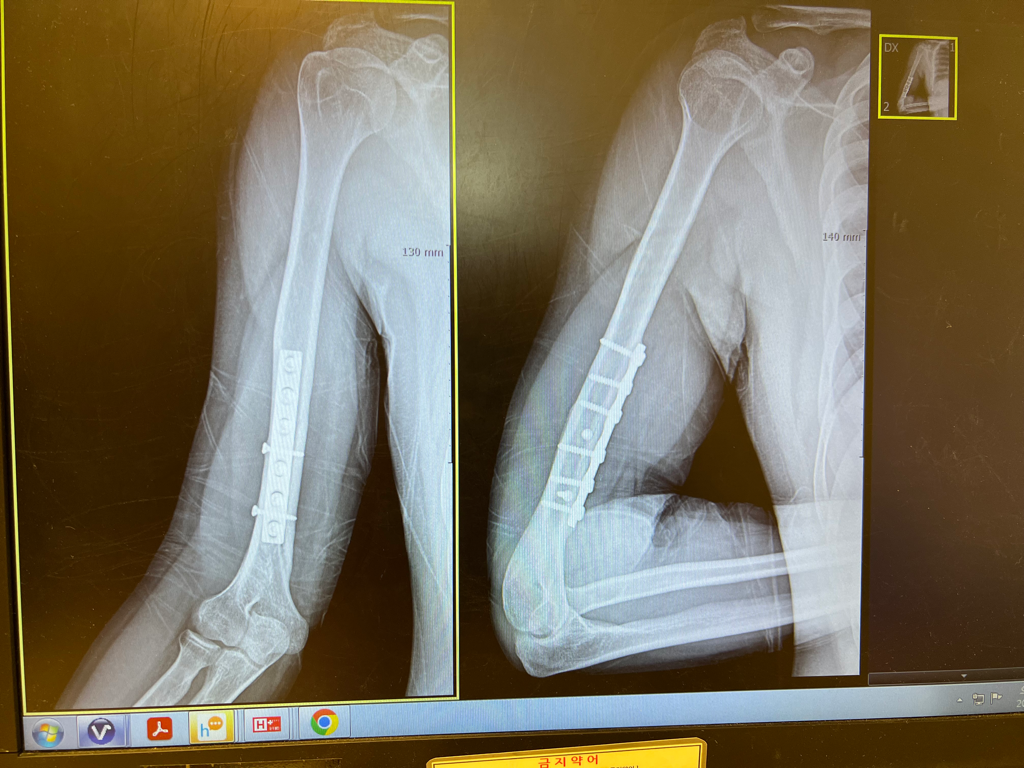

제가 5년 전쯤에 오른쪽 상완골 골절 이후 운동을 못하다가 다시 운동해도 된다는 진단 받고 헬스를 다시 시작한지

3개월 정도 됐습니다 그런데 중간중간 수술한 오른팔 팔꿈치 쪽에 통증이 있어서 트레이너분께 상담 받고

최근에 운동해도 된다는 진단 받을때 찍었던 엑스레이 사진도 같이 첨부하겠습니다 (철심은 제거하지 말라고 해서

남아 있습니다)

• 1번 째 사진